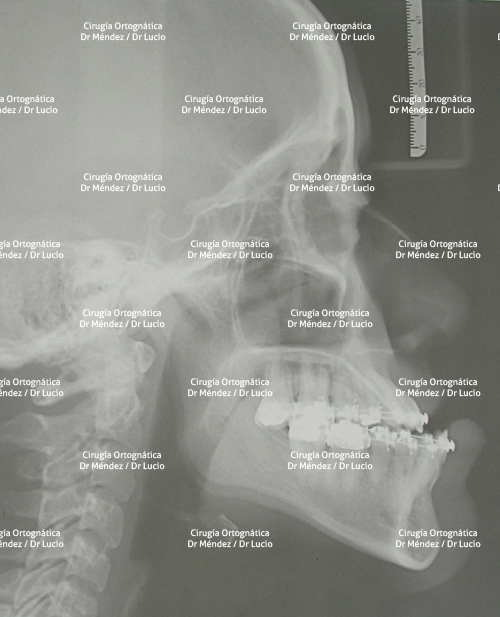

RETROGNASIA E HIPOPLASIA DEL MENTÓN Paciente operado de avance de mandíbula y mentoplastia de avance |

||